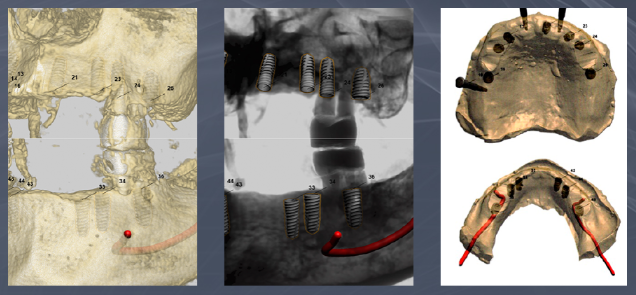

전체임플란트후기 진단

육안으로 확인이 불가능한 부분이나

치아의 배열, 간격, 얼굴 비율을

높은 정확도로 분석할 수 있는 RAY FACE,

고사양 저선량으로 안전한 3D-CT

거북하지 않은 디지털 인상채득 방식의

구강 스캐너 트리오스, itero

강남새로치과는

대학병원급 첨단 디지털 진단 시스템을 갖추고 있어

65세이상임플란트 전체임플란트의

진단의 정밀도를 높입니다.

또한 가상수술 시스템인 네비게이션 임플란트로

올바른 방향과 각도와 위치를 미리 설정할 수 있는

가이드 제작이 가능해

치료 계획의 안정성을 높입니다.